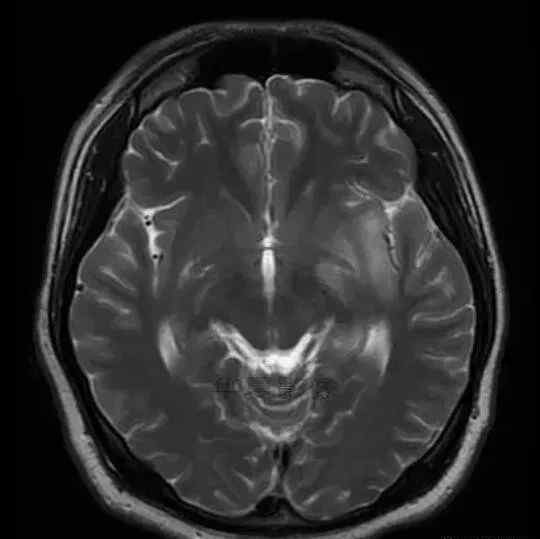

男,25岁,6天前意外感冒,现在发烧。他的体温超过39.0℃,他的呕吐物不是喷射状的。他的呕吐物是胃里的东西。

1.左侧颞叶、海马和岛叶T1WI信号低,T2WI信号高

2.病变没有明显的边界

3.占用效果不明显

4.豆状核不受影响